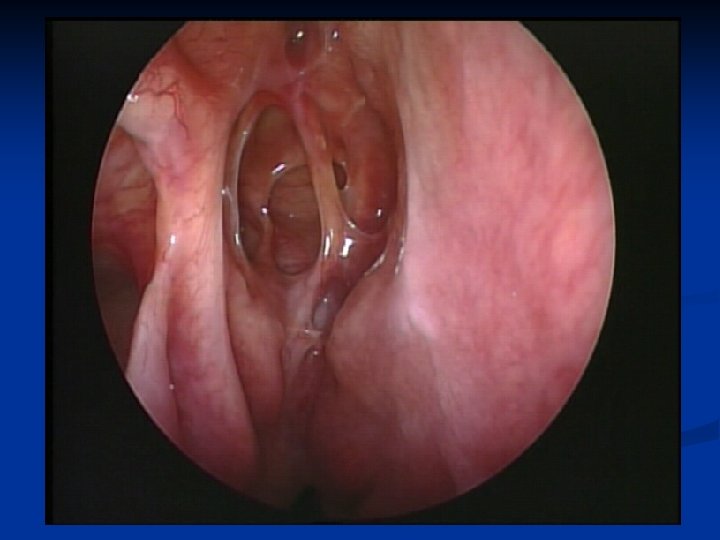

Kazuistika 2. n n n 48 ročný pacient Obojstranná FESS operácia v CA pre nosovú polypózu Predoperačne lokálne a celkovo kortikoidy 2. pooperačný deň udáva výtok čírej tekutiny z pravej nosovej dierky Na základe anamnézy, endoskopického vyš. a HRCT diagnostikovaná iatrogénne spôsobená rinolikvorea vpravo v oblasti lamela lateralis, indikovaná duraplastika vpravo

Kazuistika 3. n n n 61 - ročná pacientka FESS operácia vpravo pre nosovú polypózu s postihnutím pravej maxilárnej, čelovej dutiny a predných ethmoidov Peroperačne odstránený zo stredného nosového priechodu cystický polypózny útvar, dutiny vyplnené hlienohnisom Pacientka týždeň po operácii pri amb. kontrole udáva výtok čírej tekutiny z pravej nos. dierky Na základe anamnézy, endoskopického nálezu a HRCT diag. rinolikvorea v oblasti nazofrontálneho vývodu a stropu ethmoidov, indikovaná duraplastika vpravo Stav hodnotíme ako meningokélu s následnou rinolikvoreou